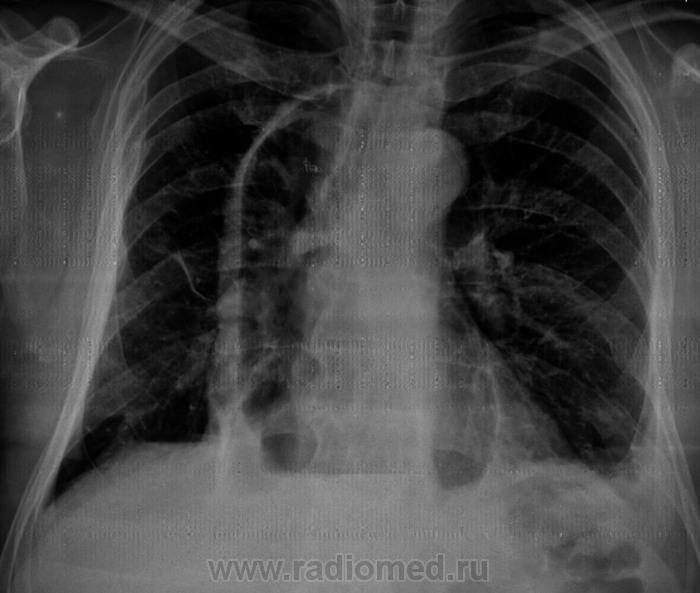

Какие мнения будут по снимкам уважаемые коллеги?

Ну очень осторожно:кишечные дела?

Хочется это явление назвать передней парастернальной диафрагмальной грыжей.

Медиастинальная грыжа. КТ собираетесь проводить?

Пластика толстой кишкой вместо удаленного пищевода по поводу рака.